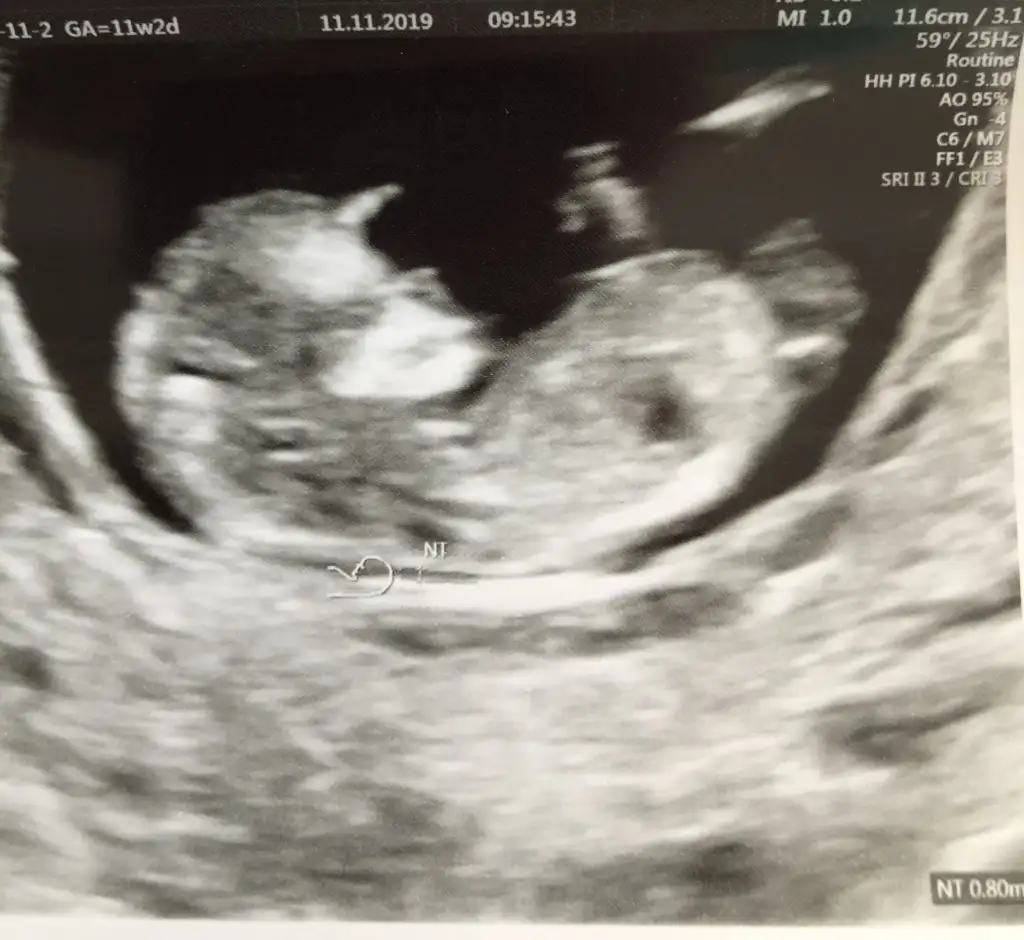

merhaba, ben de tahmin rica edebilir miyim? 11 hafta 2 günlük bebeğim :)